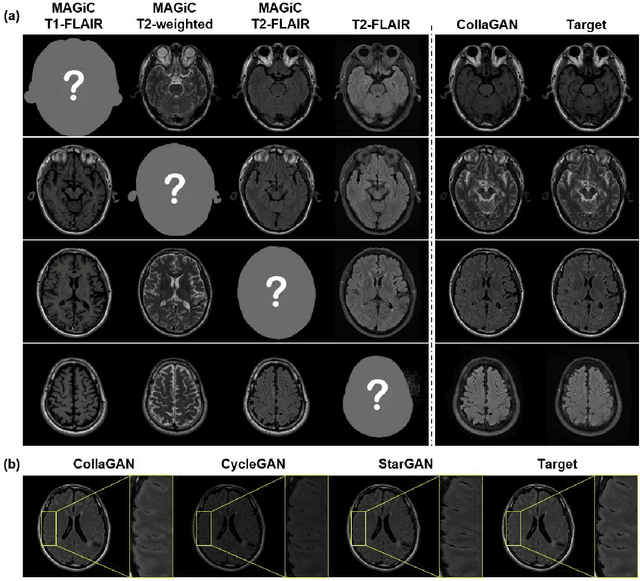

Abstract:Thanks to the recent success of generative adversarial network (GAN) for image synthesis, there are many exciting GAN approaches that successfully synthesize MR image contrast from other images with different contrasts. These approaches are potentially important for image imputation problems, where complete set of data is often difficult to obtain and image synthesis is one of the key solutions for handling the missing data problem. Unfortunately, the lack of the scalability of the existing GAN-based image translation approaches poses a fundamental challenge to understand the nature of the MR contrast imputation problem: which contrast does matter? Here, we present a systematic approach using Collaborative Generative Adversarial Networks (CollaGAN), which enable the learning of the joint image manifold of multiple MR contrasts to investigate which contrasts are essential. Our experimental results showed that the exogenous contrast from contrast agents is not replaceable, but other endogenous contrast such as T1, T2, etc can be synthesized from other contrast. These findings may give important guidance to the acquisition protocol design for MR in real clinical environment.

Abstract:In many applications requiring multiple inputs to obtain a desired output, if any of the input data is missing, it often introduces large amounts of bias. Although many techniques have been developed for imputing missing data, the image imputation is still difficult due to complicated nature of natural images. To address this problem, here we proposed a novel framework for missing image data imputation, called Collaborative Generative Adversarial Network (CollaGAN). CollaGAN converts an image imputation problem to a multi-domain images-to-image translation task so that a single generator and discriminator network can successfully estimate the missing data using the remaining clean data set. We demonstrate that CollaGAN produces the images with a higher visual quality compared to the existing competing approaches in various image imputation tasks.